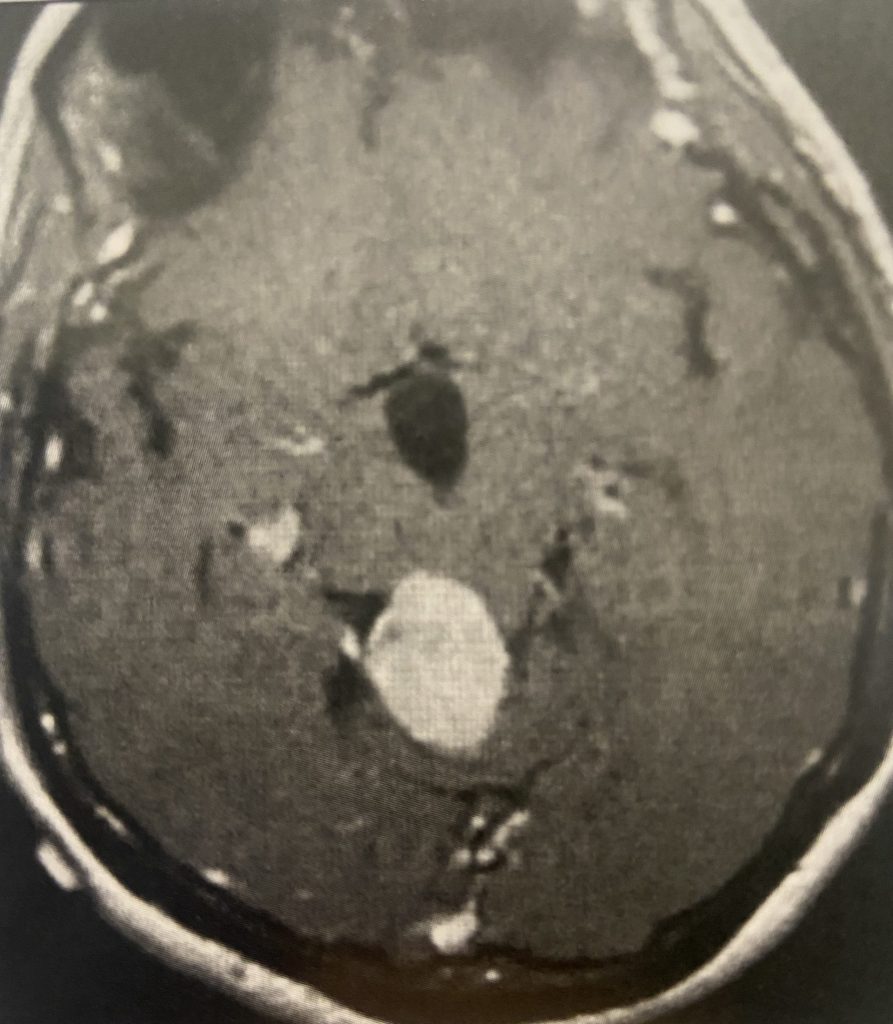

This is a 57-year-old woman with new onset memory problems and gait difficulty. MRI demonstrated a 3 cm tumor in the pineal region, most consistent with a meningioma growing inferiorly off the right tentorium.

Figure 1: Preop post contrast axial MRIs demonstrating a pineal region meningioma with hydrocephalus.

The tumor was causing compression of the upper brainstem and hydrocephalus. The tumor was removed by Dr. Michael Brisman using a right occipital / transtentorial approach.